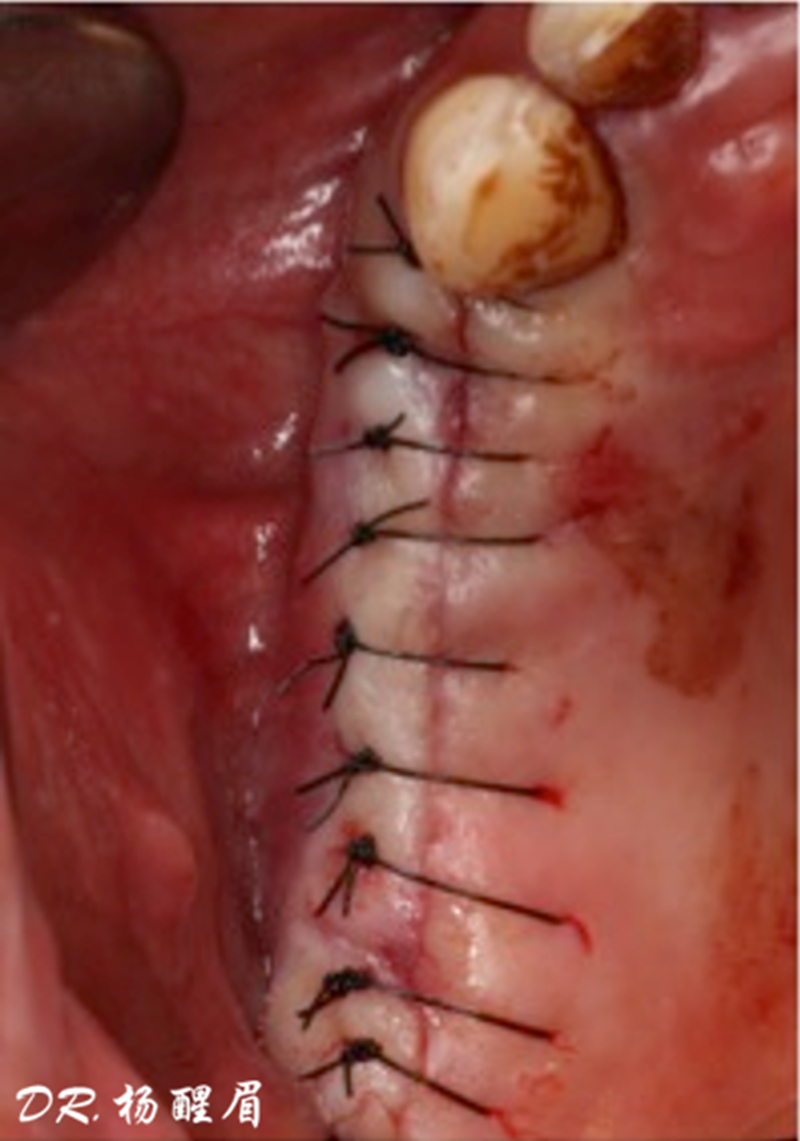

®進行縫合

®多顆植體位點及角度的精確性,確保后期修復方案順利完成,也使患者能在使用過程中承受最佳的咬合力